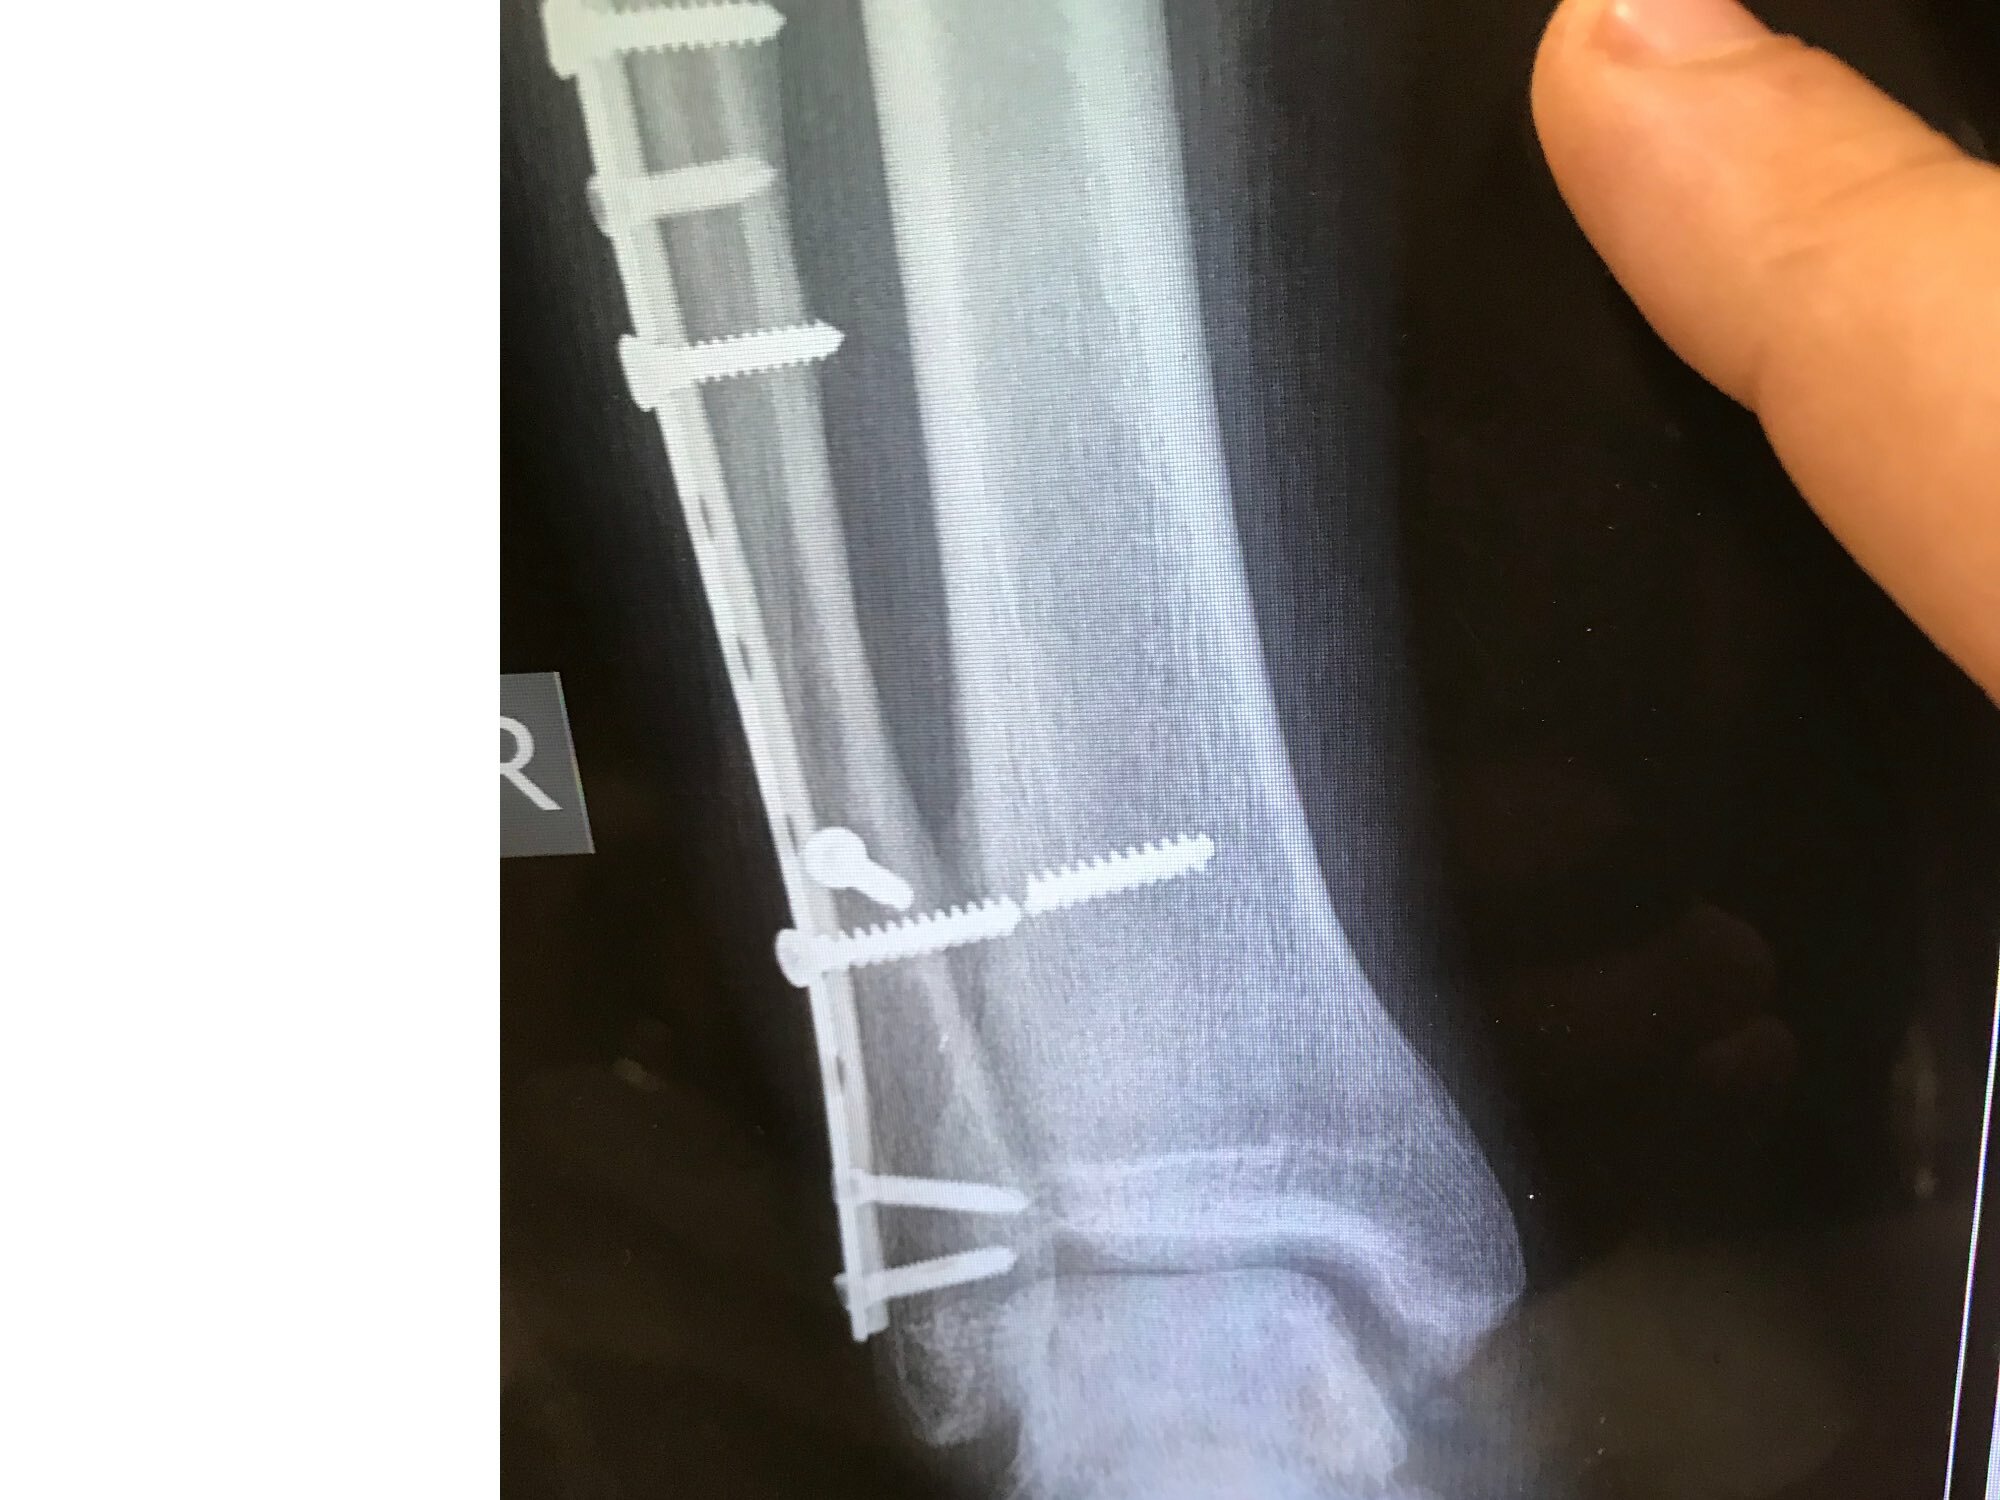

Казалось бы, зачем? Металл является хорошим материалом, и в настоящий момент титановые конструкции лидируют как заменители кости или фиксирующие ее конструкции. Титан - очень хорош: прочен биоинертен, но не идеален. Хроническая постоянная нагрузка в локальных участках импланта в результате приводит к тому что он ломается. Мы видим это довольно часто( называем это усталостным эффектом), при планировании операций и использования имплантов стараемся учитывать этот эффект.

Вот типичный пример. этот винт лучше бы выкрутить раньше, -при начале нагрузок именно в это месте будет локальная нагрузка при ходьбе и он, если не утратит стабильности, обязательно сломается.